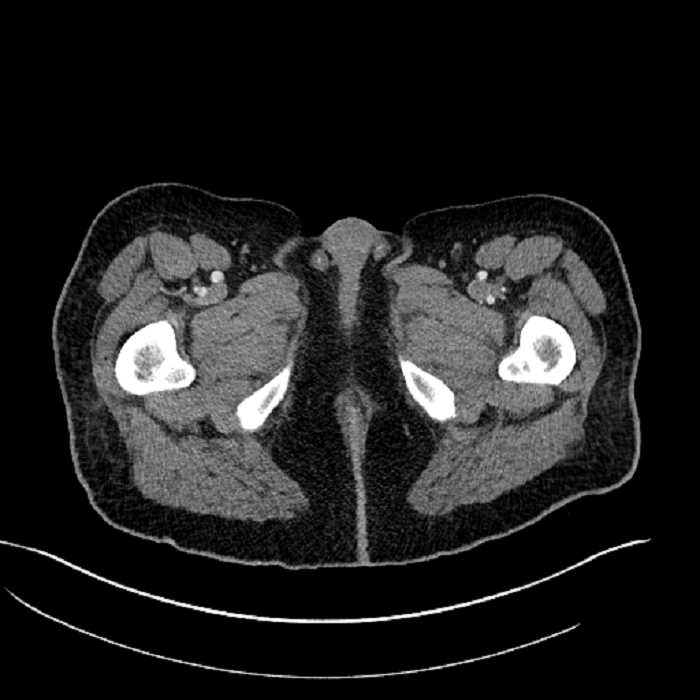

Age: 63

Sex: Male

Indication: Abdominal pain

• Mild mural thickening of a segment of the sigmoid colon with adjacent fat stranding and a 1.5 cm fluid and gas collection along the tip of an inflamed diverticulum

• Loss of the normal fat plane between this collection and adjacent loops of small bowel, which demonstrate mural thickening

Acute sigmoid diverticulitis complicated by a small contained perforation and a large abscess in the right hepatic lobe. Additional small subcapsular abscesses along the anterior margin of the left hepatic lobe.

Additionally, loss of the normal fat plane between the peridiverticular collection and adjacent thickened loops of small bowel raises the potential for an enterocolonic fistula.

Hepatic abscess showing the double target sign with low density internally surrounded by a thin inner enhancing rim (red arrow) and ill-defined outer low density rim (yellow arrow). Blue arrow indicates an internal septation. Red arrows: additional smaller subcapsular abscesses. Red arrow: focal contained perforation associated with diverticulitis.